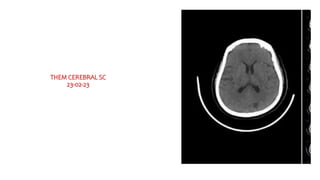

THEM CEREBRAL SC

23-02-23